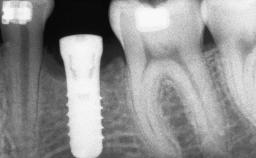

A 47-year-old Caucasian woman with a single-tooth edentulous space at the site of the left maxillary canine was referred for treatment. She had undergone traumatic extraction of this impacted canine several months before referral. Her chief complaint was the dissatisfying appearance of her smile. The patient desired a stable and esthetic rehabilitation of the site. Her dental history showed no evidence of periodontal disease or bruxism. She had no systemic diseases, was not taking any medications, and did not smoke. The extraoral examination revealed a high lip line and an inadequate soft-tissue volume at the defective canine site. Large black triangles were visible between the canine and its adjacent teeth.

Bone Augmentation Staged|Vertical

Augmentation Materials Autogenous chips|Membrane

Bone Volume Horizontally and vertically sufficient Horizontally deficient Deficient vertically or deficient vertically AND horizontally

Bone Volume Deficient vertically or deficient vertically AND horizontally